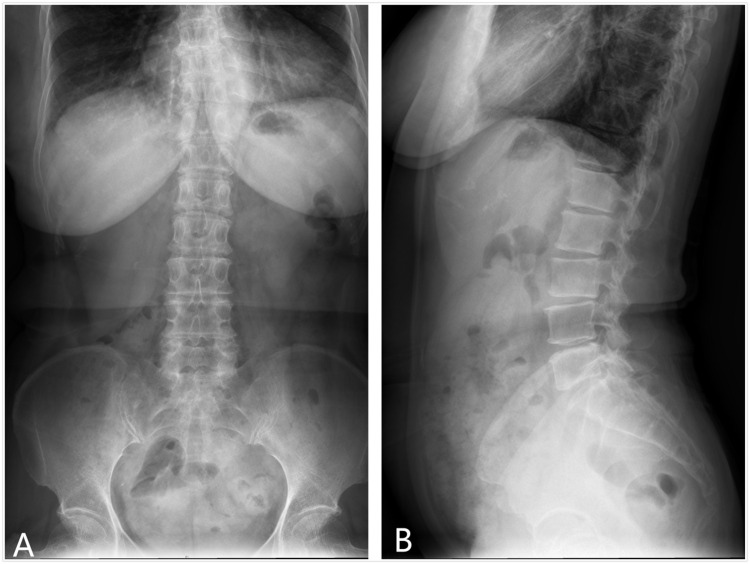

Methods: From February 1, 2020, to February 1, 2023, 13 patients with discogenic back pain from painful SNs (confirmed via intraoperative discography) who underwent single-level PELD at the index SN level were enrolled in the current study. Clinical data were retrospectively analyzed. Outcome measures, including the visual analog scale (VAS) for back pain and the Oswestry Disability Index (ODI), were recorded preoperatively and at 1 day, 6 months, and 12 months postoperatively. MRI scans of the lumbar region for all patients were evaluated preoperatively and again at the one-month follow-up.

Results: All 13 patients were successfully treated with percutaneous endoscopic lumbar discectomy (PELD), showing significant postoperative improvements in VAS and ODI scores. Postoperative lumbar MRI revealed degenerative disc material in the SN cavities, which was removed using PELD. No surgical issues such as infections or nerve root damage, were noted.

Conclusion: Postoperative MRI confirmed the removal of degenerative disc material, reinforcing PELD's efficacy in treating the pathological changes associated with painful SNs. No surgical complications, such as infections or nerve root damage, were seen, underscoring the safety of PELD. This study demonstrates that PELD effectively manages discogenic lower back pain caused by SNs.